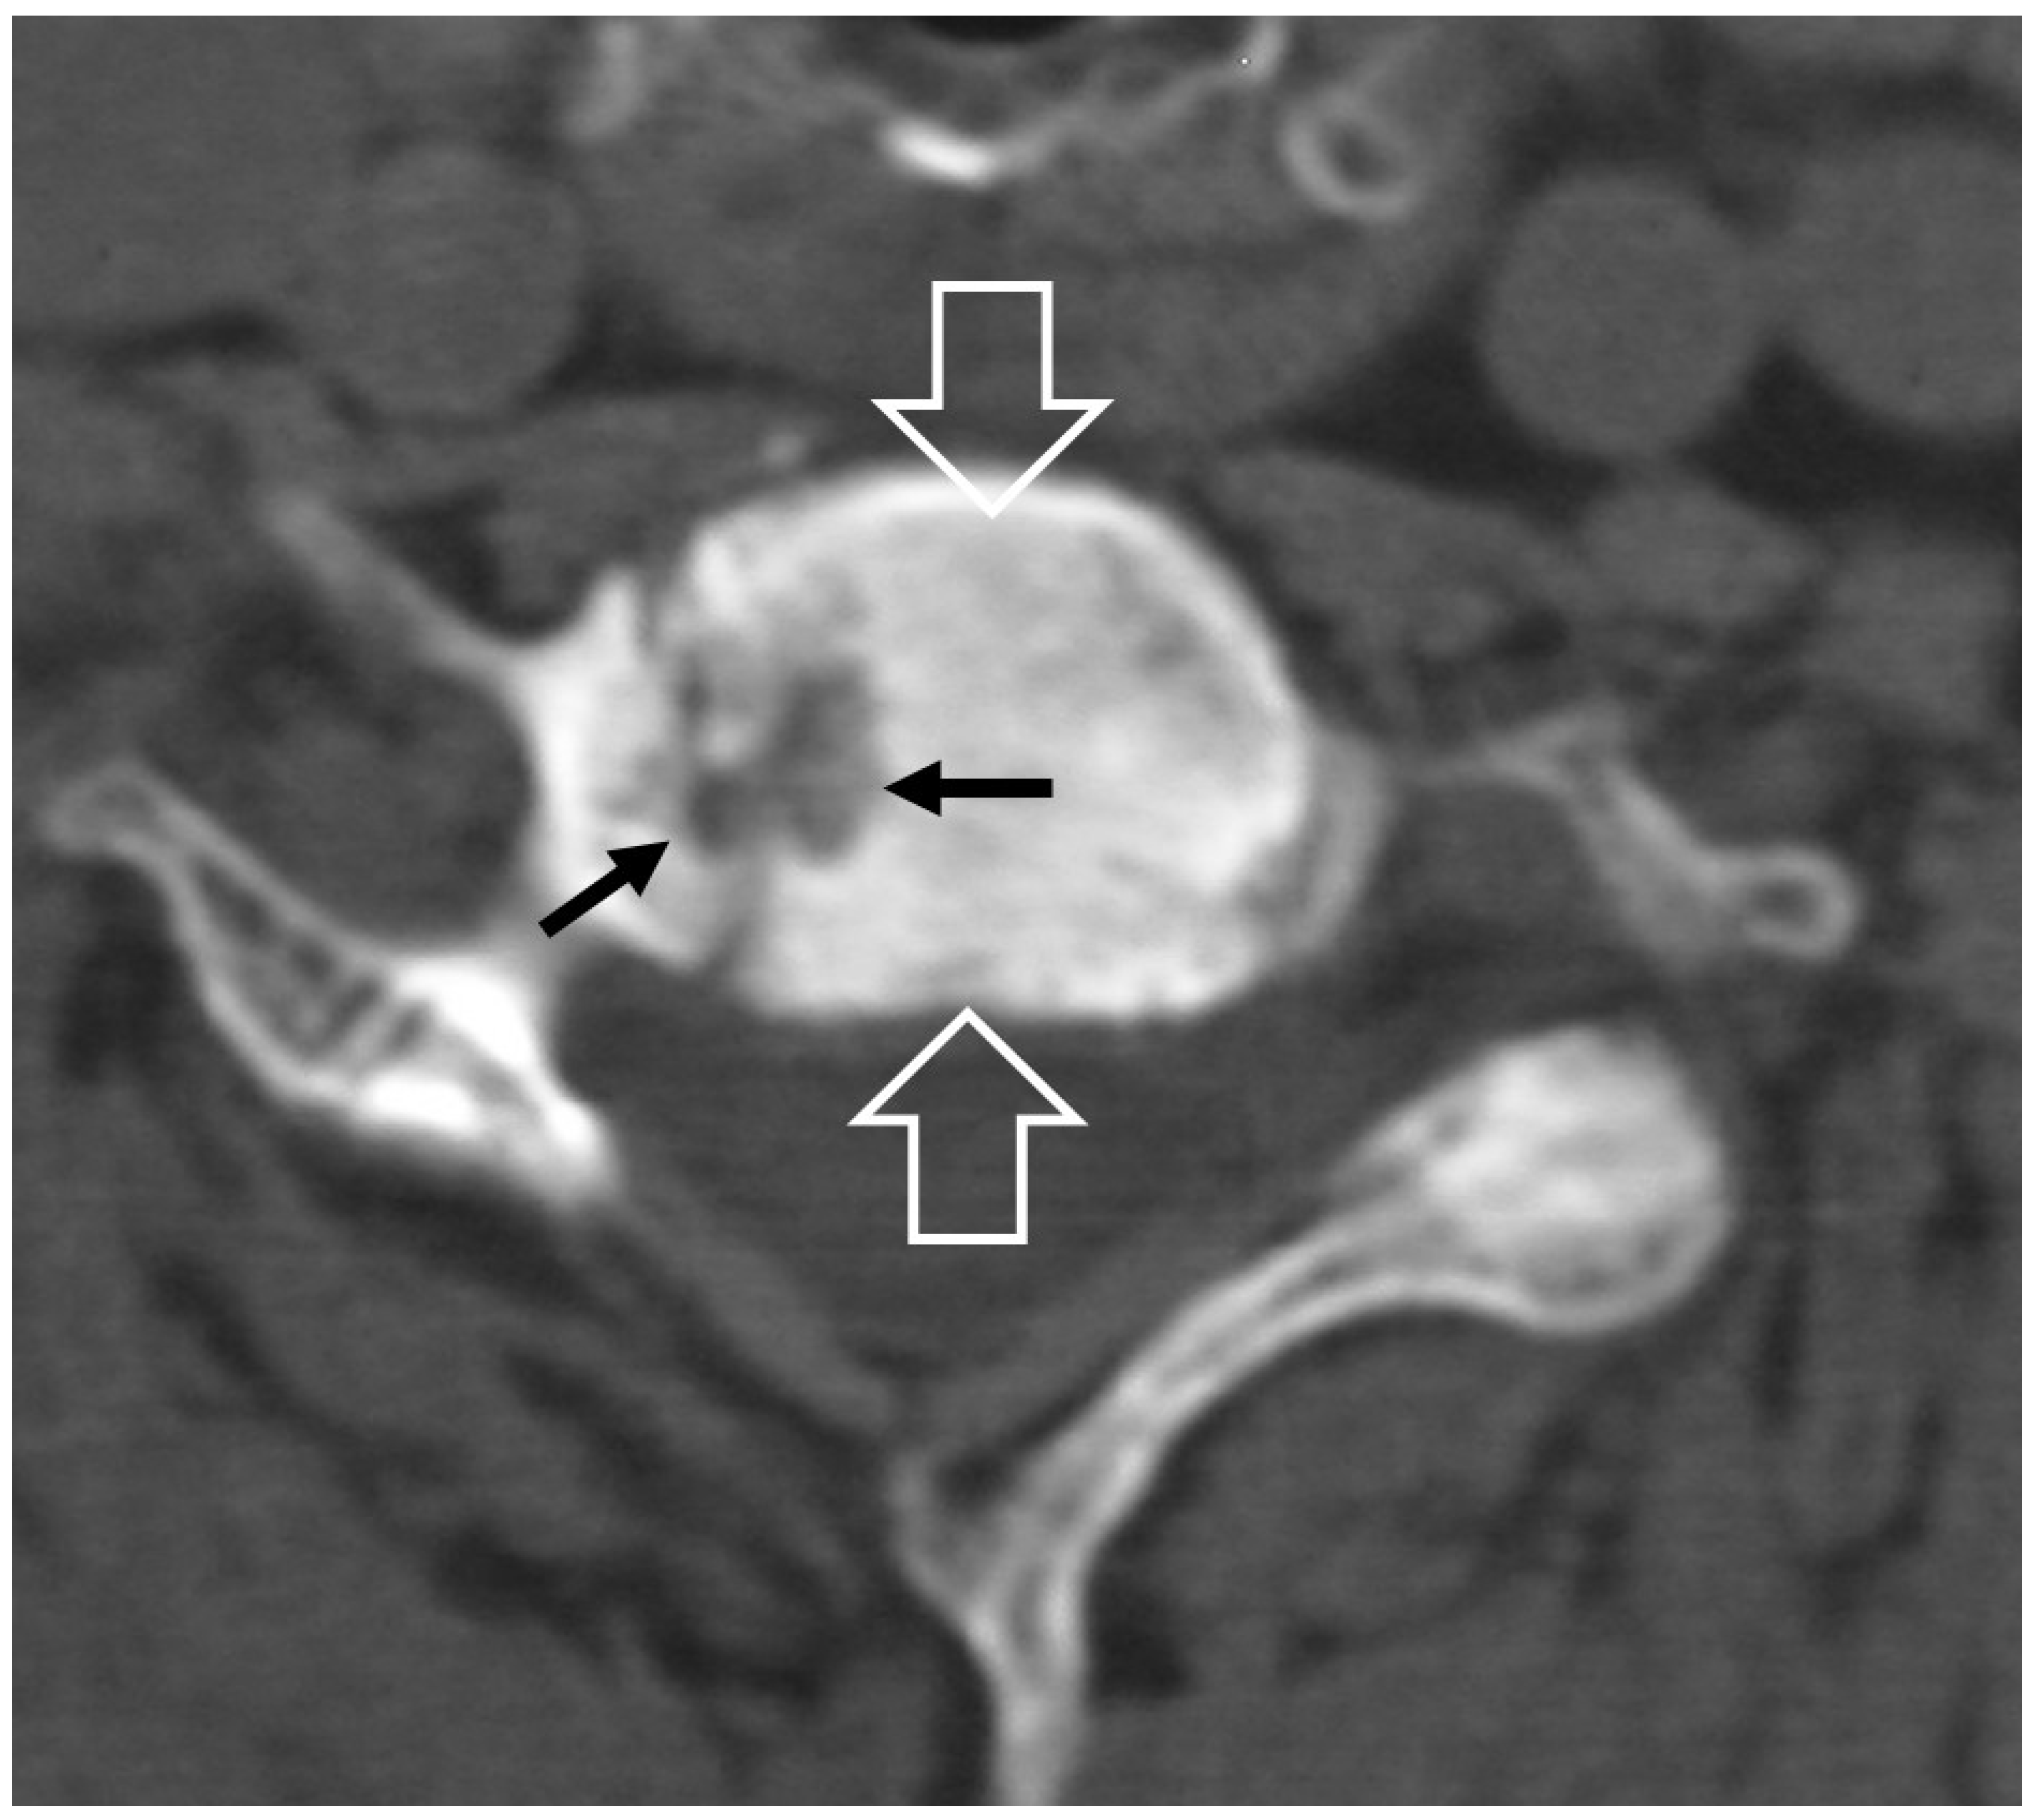

2.1.5. Crystal Deposition

- Ring, D.; Vaccaro, A.R.; Scuderi, G.; Pathria, M.N.; Garfin, S.R. Acute calcific retropharyngeal tendinitis. Clinical presentation and pathological characterization. J. Bone Jt. Surg. Am. 1994, 76, 1636–1642. [Google Scholar] [CrossRef] [PubMed]

- Offiah, C.E.; Hall, E. Acute calcific tendinitis of the longus colli muscle: Spectrum of CT appearances and anatomical correlation. Br. J. Radiol. 2009, 82, e117–e121. [Google Scholar] [CrossRef] [PubMed]